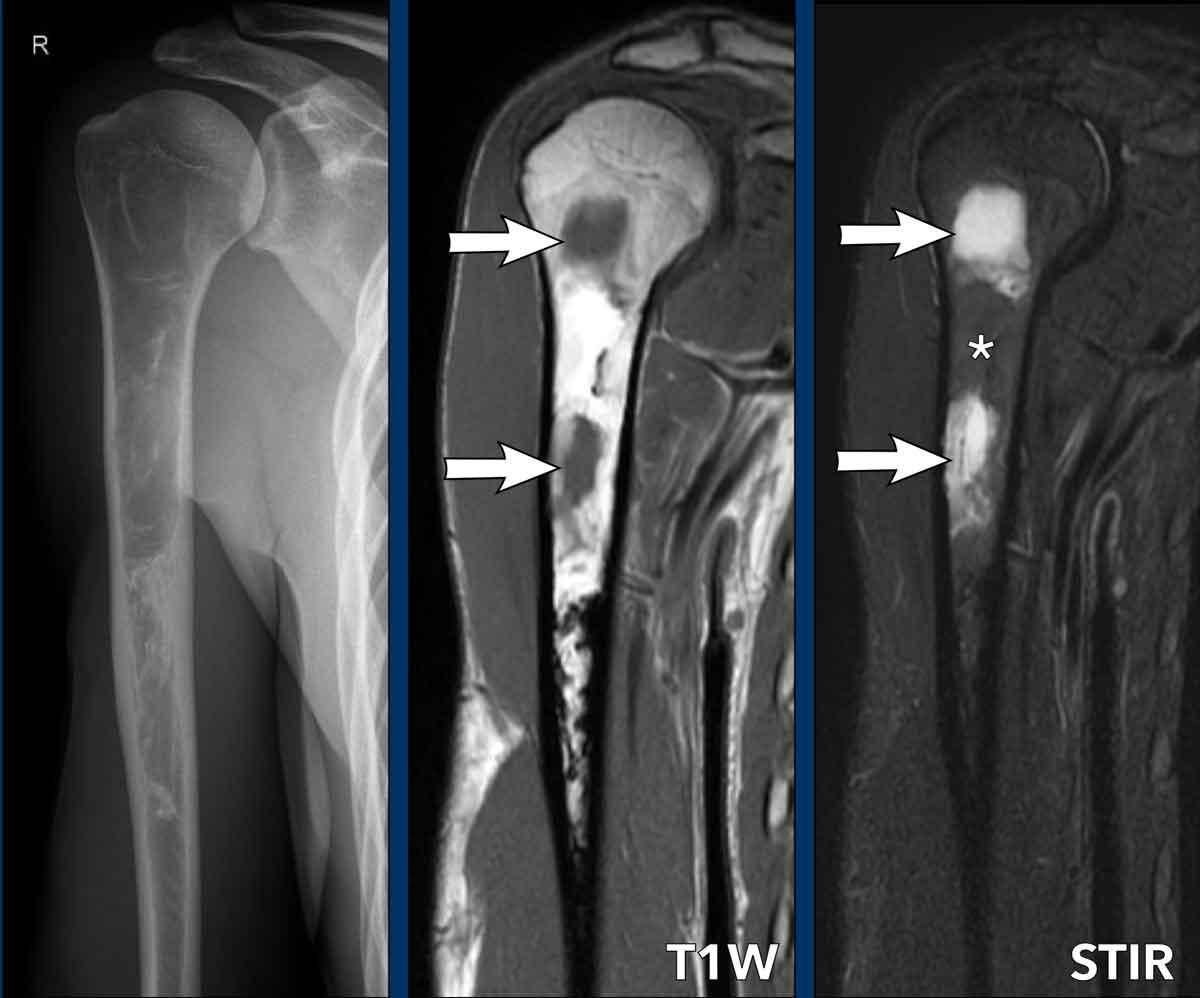

Hình ảnh

Hình ảnh X-quang xương cánh tay phải của bệnh nhân 26 tuổi cho thấy một tổn thương lớn lấp đầy ống tủy của vùng hành xương và thân xương cánh tay gần, với hình ảnh tiêu xương và kính mờ cùng các thành phần đặc xương hơn ở phía xa.

Không có phản ứng màng xương hoặc các đặc điểm xâm lấn khác.

Dựa vào độ tuổi và hình ảnh này, Loạn sản xơ (FD) có thể là chẩn đoán phù hợp.

MRI đã được thực hiện để đánh giá chi tiết hơn trong trường hợp này.

Hình ảnh T1 và STIR mặt phẳng coronal cho thấy các thành phần dạng nang trong tổn thương, biểu hiện giảm tín hiệu trên T1W và tăng tín hiệu trên STIR (mũi tên). Đây là những đặc điểm điển hình của loạn sản xơ (FD).

Giữa các vùng nang là mô mỡ, biểu hiện tăng tín hiệu trên T1W và bị xóa tín hiệu trên STIR (dấu hoa thị).

Lưu ý phần xa của tổn thương có tín hiệu rất thấp tương ứng với vùng xơ cứng trên X-quang.

FD có thể xuất hiện không đồng nhất và chứa các thành phần sụn liền kề với các vùng nang hoặc xơ cứng.

Không cần sinh thiết vì những phát hiện này phù hợp với FD đơn xương.